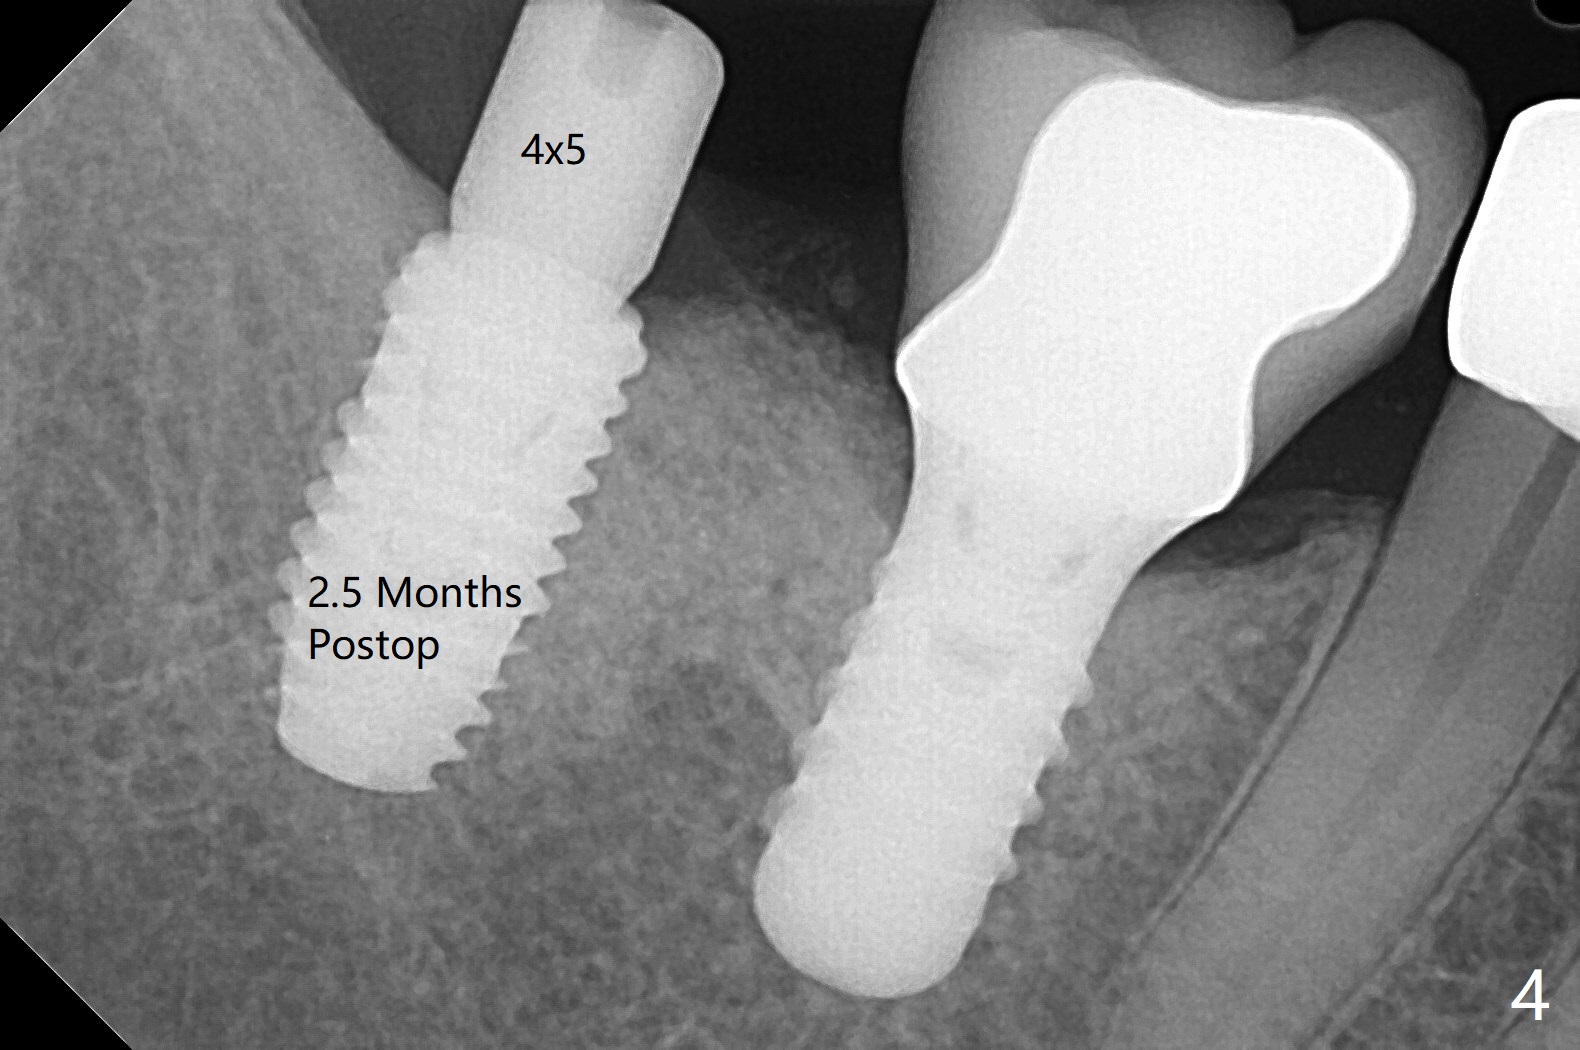

61岁女右下7导板钻洞,第一个钻头(环形钻)就有困难入位,部分磨去对合7近中腭侧牙尖(图一:*),钻头入位就好多了(图二:^,对比)。钻洞时发现骨质密度中等,所以最后钻头直径4.5毫米。不过无法用手植牙工具旋入植体,使用5.0毫米功螺纹钻头后,手工具就好用了,植体植入一定深度,扳手有空间插入,最后扭力30Ncm。第二个问题,当按照设计深度植入植体,用探针检查颊侧好像没有骨壁;加深大约0.5毫米(仿佛没有取到目的,颊侧骨板不明显)后,使用6毫米profile钻头,插入5.5x3毫米愈合基台(图二,三),在基台和颊侧牙龈之间植入异体骨粉,但愿帮助颊侧骨板再生。术后一周内敷料脱落,颊侧伤口愈合,好像骨粉没有流失。术后2.5月愈合基台脱落,换至小号基台(4向毫米),仍旧疼痛,休息2分钟,手拧紧,拍摄根尖片,仿佛就位(图四)。准备一周后调换稍微大,例如,4.8毫米基台。术后3.5个月,5.2毫米基台好像没有就位(图五:<),可能与远中牙槽嵴接触(*)。小一号基台仿佛就位(图六),与远中牙槽嵴无接触。术后4个月粘固后基台螺丝拧紧30Ncm。术后8个月,也就是粘固后4个月,牙槽嵴似乎试图覆盖植体平台(图七:箭头)。